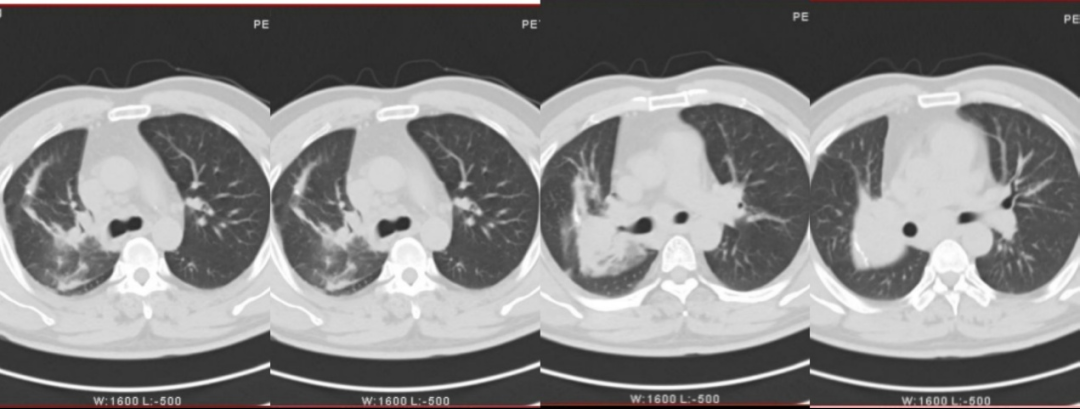

四年后,命运却给了他狠狠一击。2024年,王先生开始察觉身体不对劲。走几步路就喘,胸闷,有时候感觉气吸不进去。家人连忙带他复查,胸部CT显示,他的右肺门和当年手术的吻合口处,长出了软组织肿块,还伴有多发淋巴结转移。

多学科合作后,为王先生制定了一个“化疗联合三代ALK靶向药”的个体化方案,同时辅以放疗。治疗过程险象环生——放疗期间出现3度放射性食管炎,吃不下饭;接着又发生重度骨髓抑制,一度危及生命。但在团队精准对症和全力抢救下,王先生一次次转危为安。

两年过去了。最近一次复查胸部CT显示:原发病灶显著缩小,转移淋巴结持续消退。王先生恢复了正常生活,能走能跑,不再喘憋。